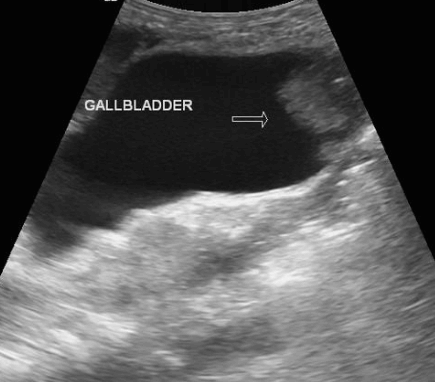

US finding

- 담낭벽 석회화에 의한 소견으로 후방음향음영을 동반한 곡선모양의 고에코를 나타내는 것

- 전벽과 후벽 모두 고에코를 나타내는 것

- 음향음영을 동반하는 불규칙한 고에코가 군집형태를 이루는 것 (암의 가능성이 높다)

- 환자 체위에 따른 변화가 보이지 않는다

- 담낭 내강을 관찰하기 어렵다